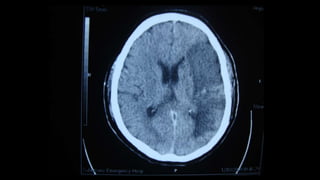

Hemiparesis with facial weakness: brain CT scan or brain MRI, with or

NB: Urgent non-contrast brain CT scan is the most suitable imaging

modality in patients with acute hemiparesis because of its availability in

Emergency Departments (usually), and it is rapid (the period of the test

is very brief (compared to MRI). Drawback: poor visualization of

posterior fossa structures because of boney artifacts, except in